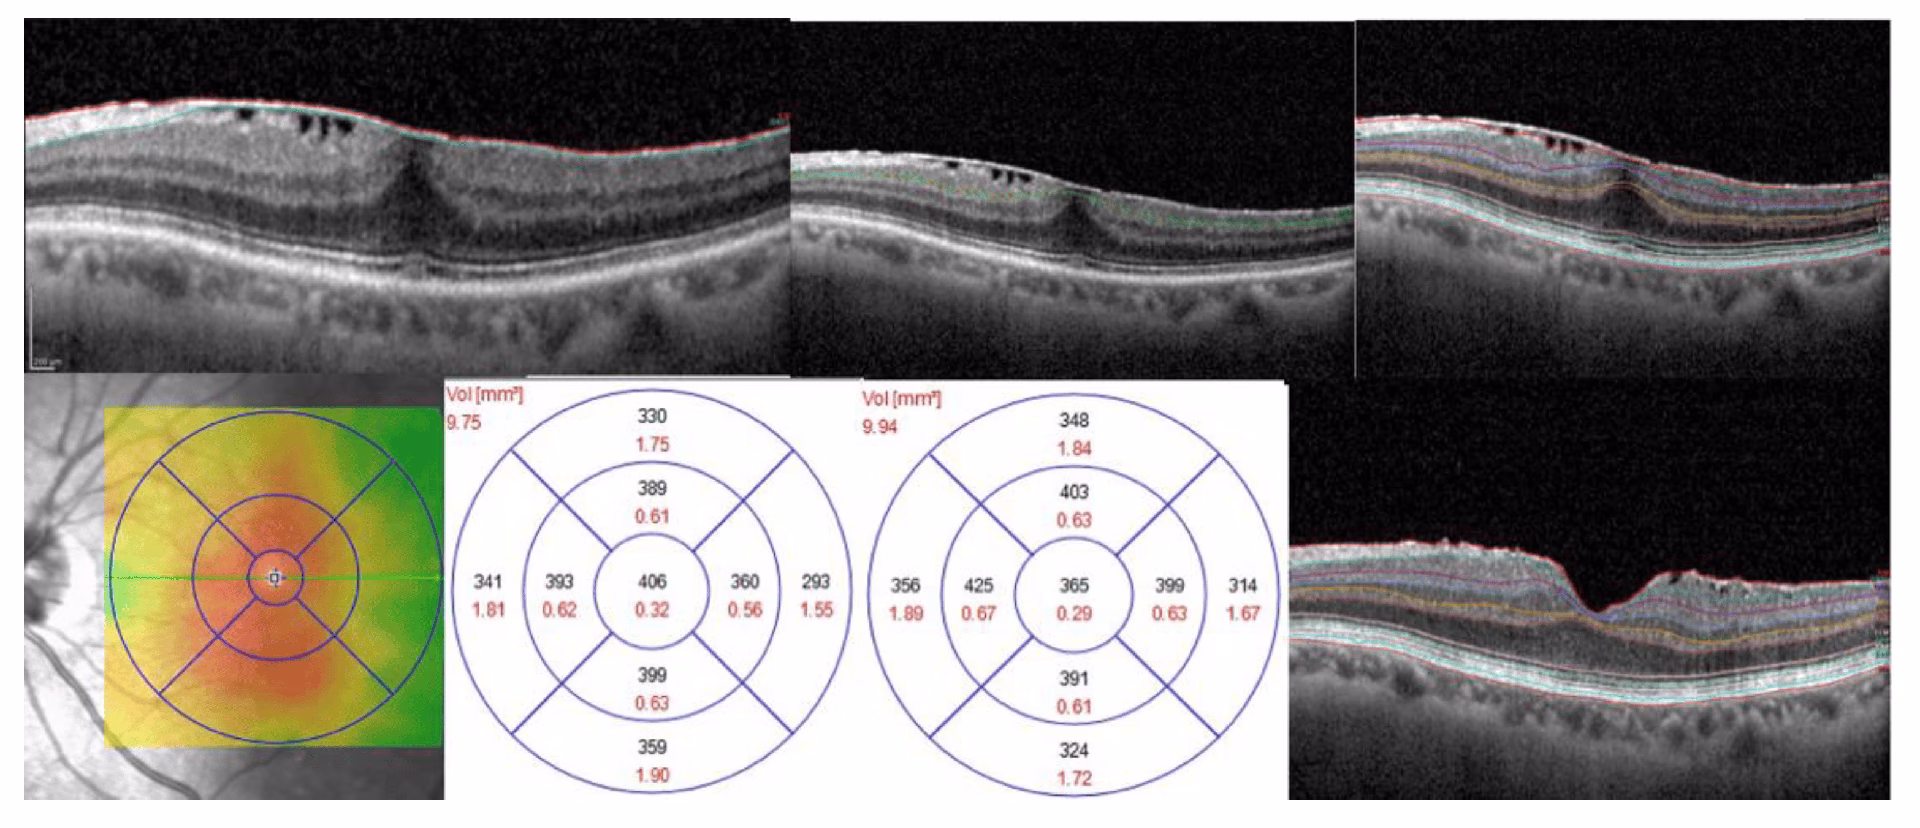

For at forstå helingsprocessen er det vigtigt først at forstå selve tilstanden. Dit øje er fyldt med en geléagtig substans kaldet glaslegemet. Med alderen kan dette glaslegeme skrumpe og trække sig væk fra nethinden – en proces kaldet posterior glaslegeme-løsning (PVD). Dette er en normal del af aldringsprocessen, men nogle gange kan det stimulere dannelsen af et tyndt lag arvæv på overfladen af makula. Makula er den lille, men ekstremt vigtige del af din nethinde, der er ansvarlig for dit skarpe, detaljerede centralsyn, som du bruger til at læse, genkende ansigter og køre bil. Når denne membran, eller ERM, trækker sig sammen, krøller den den underliggende makula, hvilket fører til de karakteristiske synsforstyrrelser.

Det er ikke alle med en ERM, der har brug for operation. Hvis membranen er mild og ikke påvirker synet i væsentlig grad, vil øjenlægen ofte blot observere tilstanden. Operation, en såkaldt vitrektomi med membranpeeling, anbefales typisk kun, når synsforvrængningen (også kendt som metamorfopsi) begynder at forstyrre daglige aktiviteter som læsning eller bilkørsel.